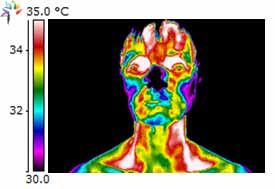

Dental Case Study 3

Upper right 1st permolar – necrotic

Lower right bridge with necrotic tooth